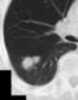

Necrotizing pneumonia